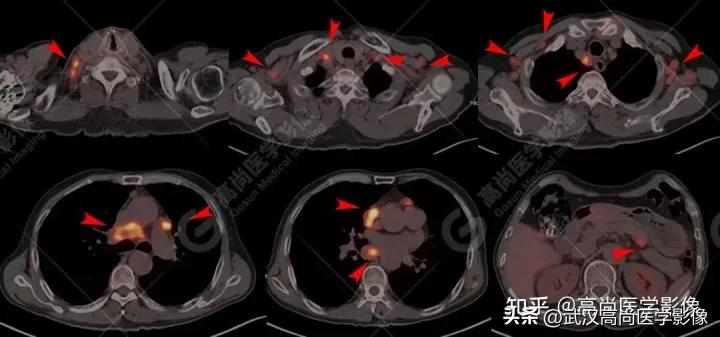

病例二

男性70岁,因胸闷、气促入院。

检查发现肝脏、腰椎异常,多发淋巴结肿大。

查血提示多项肿瘤指标升高。

全身PET/CT

肝内多发片块状、团状FDG高摄取,SUVmax18.0,CT示弥漫低密度影,CT值约35Hu,边界欠清。

影像表现:

双侧锁骨区、左侧内乳区、双侧肺门、纵隔(1R、2、3A、4R、5、6、7、8、9组)、心底部、胰胃间隙多发淋巴结肿大,FDG高摄取,SUVmax16.3。

全身多处骨质成骨性破坏,FDG高摄取,SUVmax16.3。

左侧小脑半球两处等密度结节,FDG高代谢,SUVmax12.2。

灶周无水肿,普通CT平扫确实难发现病灶,PET通过代谢增高发现。

若PET代谢无增高,一些隐匿性的小病灶需结合MR检查。

右肺下叶背段见一实性结节,大小约2.0cm×1.6cm×1.8cm,CT值33Hu,FDG高摄取,SUVmax13.0。

恶性CT征象:

病灶边缘分叶、短毛刺,其近端亚段支气管截断,瘤肺界面清楚,病灶远端片絮状阻塞性炎症。

PET/CT诊断结论

右肺下叶背段周围型肺癌,伴多发淋巴结、左侧小脑半球、肝脏、骨多发转移。